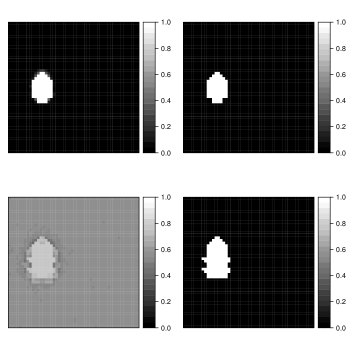

Figure 8 displays the posterior probability map for hippocampus inclusion, along with the point-wise standard deviations. The highest probabilities of inclusion are near the centers of the two regions. There is considerable uncertainty about the edges. If a researcher were only interested in the hippocampal volume for the patient, these probabilities could be used directly to estimate the volume, as discussed below.

As already mentioned, only healthy brains are used as atlases. The systematic differences are not completely captured by atlas-target image dissimilarities. Despite accounting for image dissimilarity, there is a tendency for the established methods to over-segment the hippocampus. The Bayesian label fusion model facilitates explicit incorporation of the estimated gray matter pattern as a predictor. Our prior specification allows for the possibility that the tissue classes are incorrectly assigned in some places, but are mostly reliable. The effect of the gray matter segmentation as auxiliary information can be clearly seen by comparing it even with our own model in which this information is ignored but the model is otherwise identical. Figure 10 displays the posterior inclusion probabilities obtained without using the gray matter information, along with the results already presented for reference. Using only the intensity-similarity-weighted distance labels yields a Bayesian regression analogue to the other approaches that only weight by intensity similarity. The additional tissue class information is able to prevent oversegmentation of the diseased structure.

In practice, an anatomical structure is segmented to obtain important information such as its volume or average image intensity within the structure. In our case, segmenting the hippocampus is a step toward estimating its volume. If we only obtain a binary map, then the only way to estimate the volume is by summing the indicators. Doing so ignores many sources of uncertainty, including image pre-processing, registration error, biological variation, and rater variability. Monte Carlo sampling also facilitates estimation of a distribution of plausible volumes through , defined in Section 3. Figure 11 displays the marginal volume densities for the diseased brain of interest, both with and without gray matter included in the Bayesian label fusion model. Vertical lines indicate the manually-segmented volume and the volume estimates from the other procedures considered. The benefit of including the gray matter information is again evident with the improved agreement of the volume distribution with the manual segmentation. In this case, though, we see that even without the gray matter information the Bayesian model outperforms the three majority voting procedures.